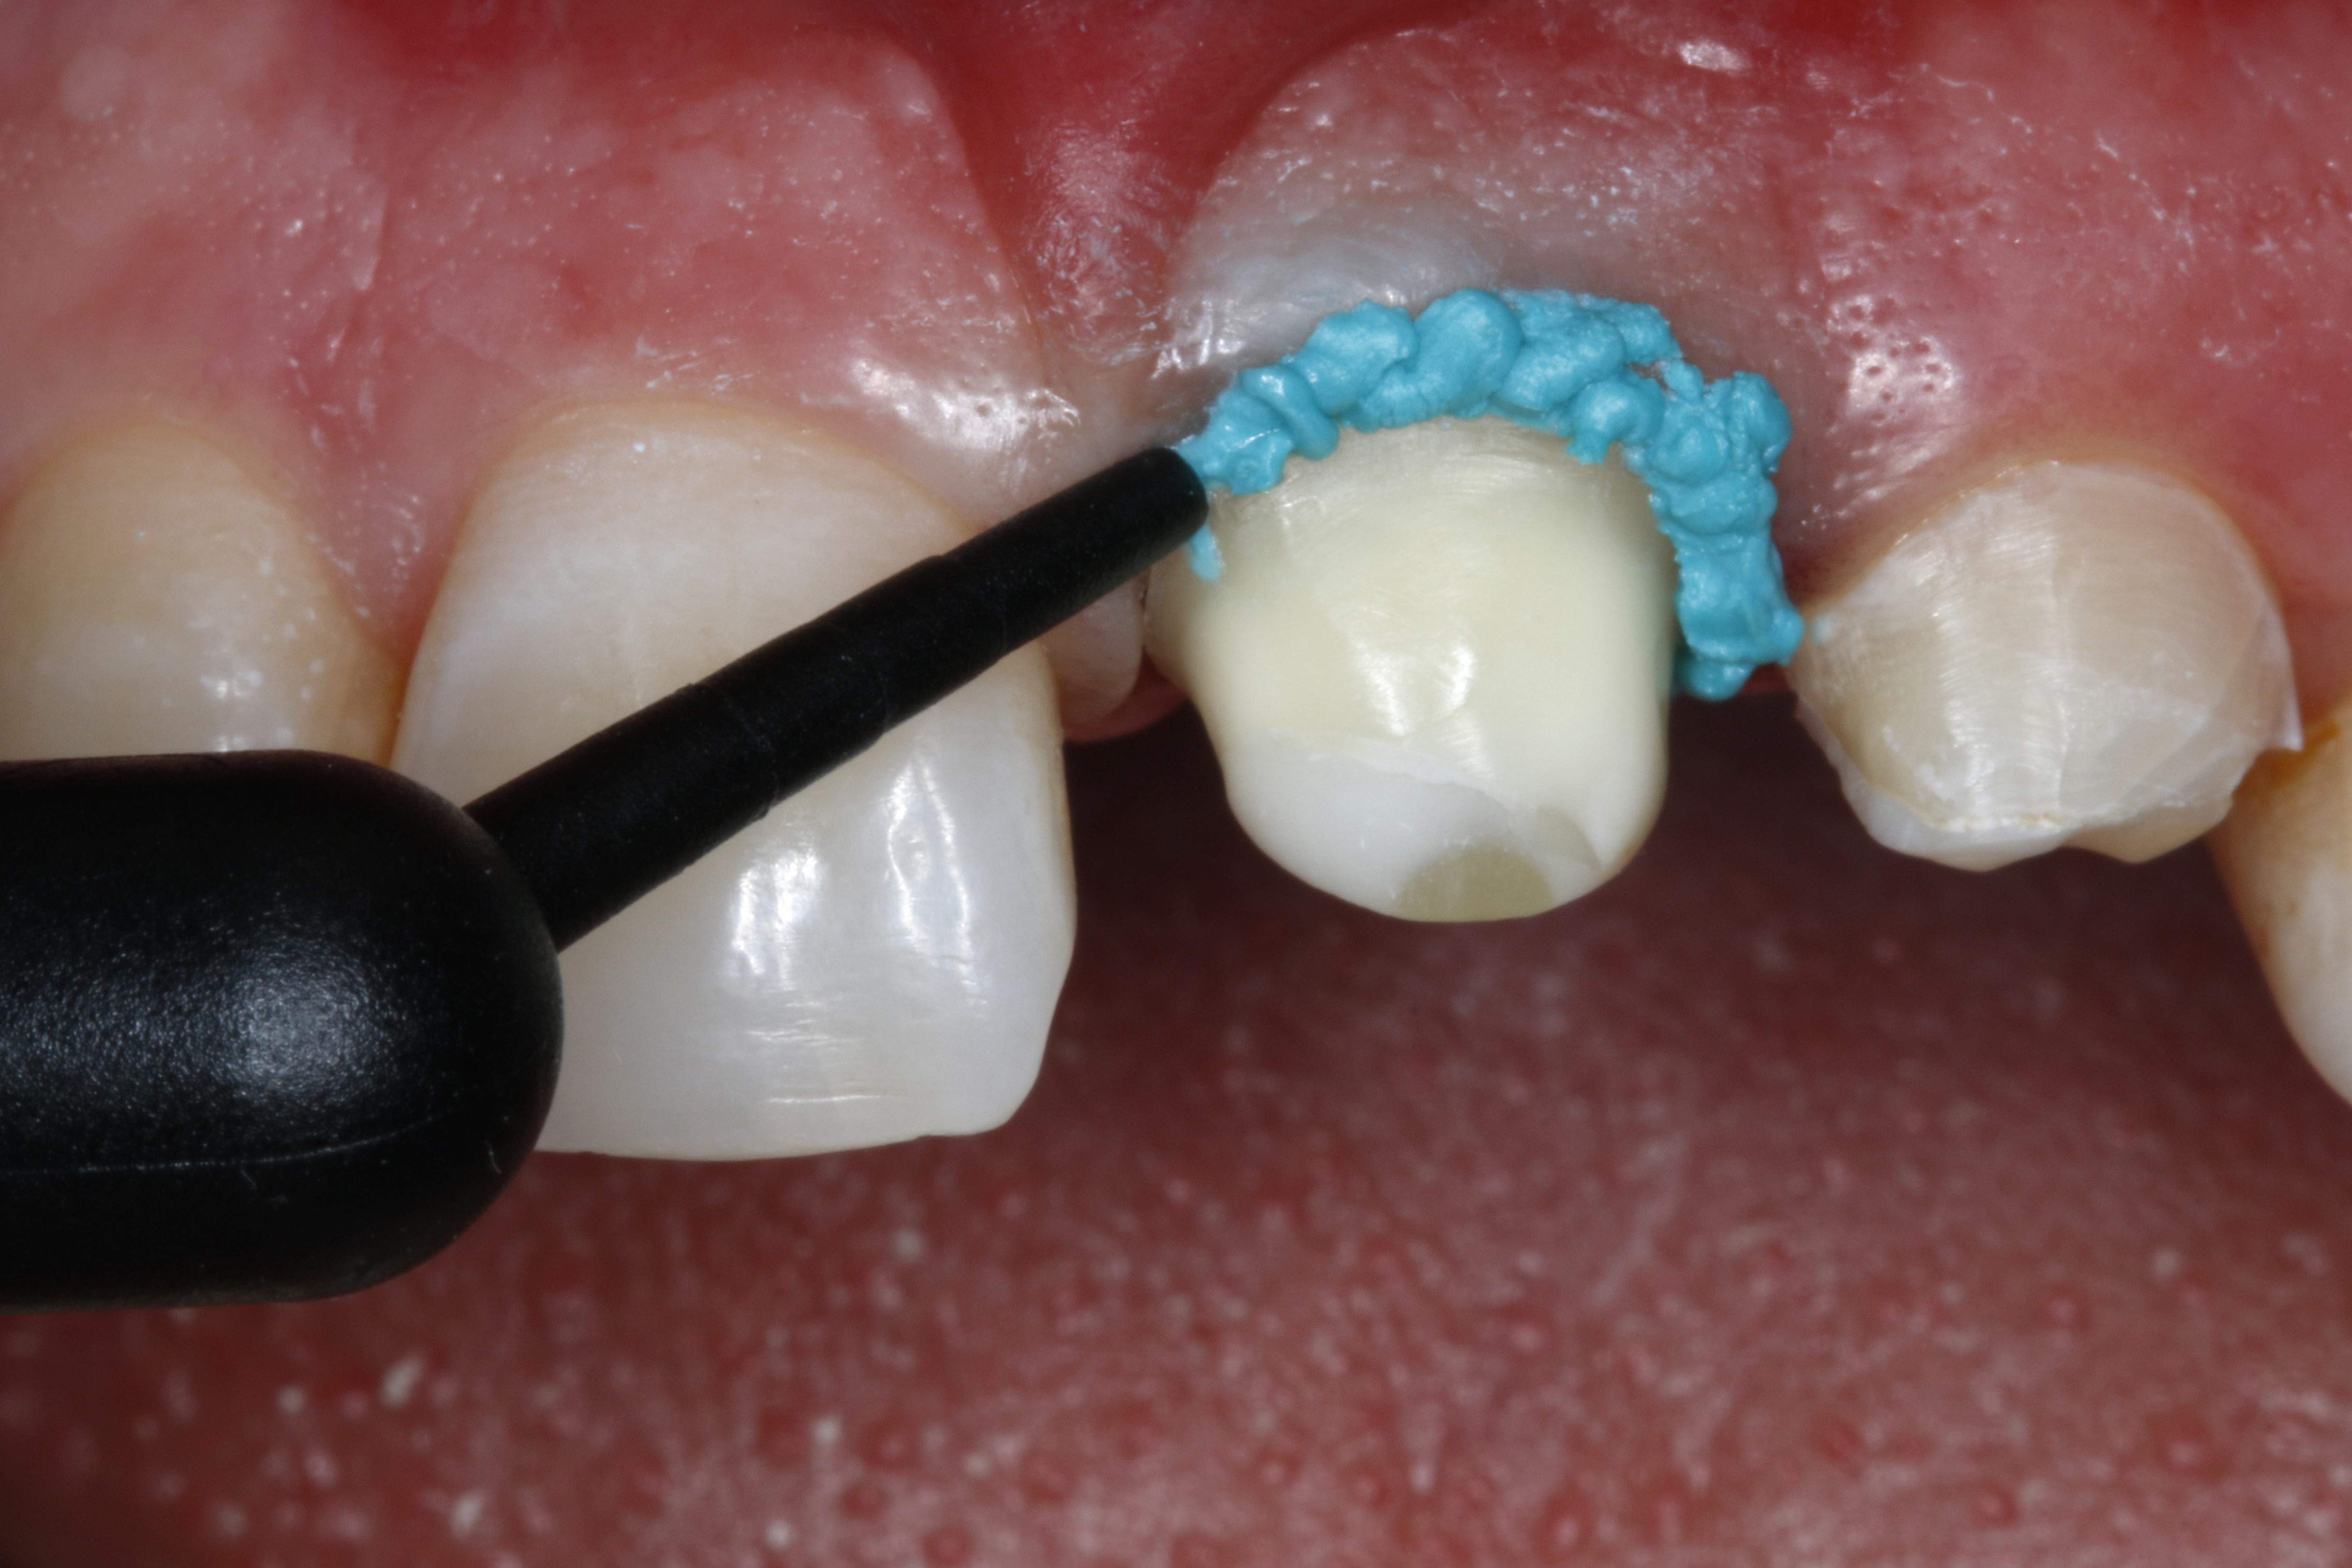

Ryc. 5. Po wprowadzeniu do szczeliny wokół zęba 21 bardzo cienkiej nici retrakcyjnej (w rozmiarze 000) wyciśnięto okrężnym ruchem pastę retrakcyjną przez bardzo cienką, zwężającą się kaniulę (pasta retrakcyjna, VOCO).

Ryc. 6. Pasta retrakcyjna jest łatwa do aplikacji, a zarazem ma dostatecznie gęstą konsystencję, aby pozwalała na dodatkowe poszerzenie szczeliny. Jednocześnie dochodzi do zatrzymania ewentualnego miejscowego krwawienia tkanek miękkich związanego z preparacją.